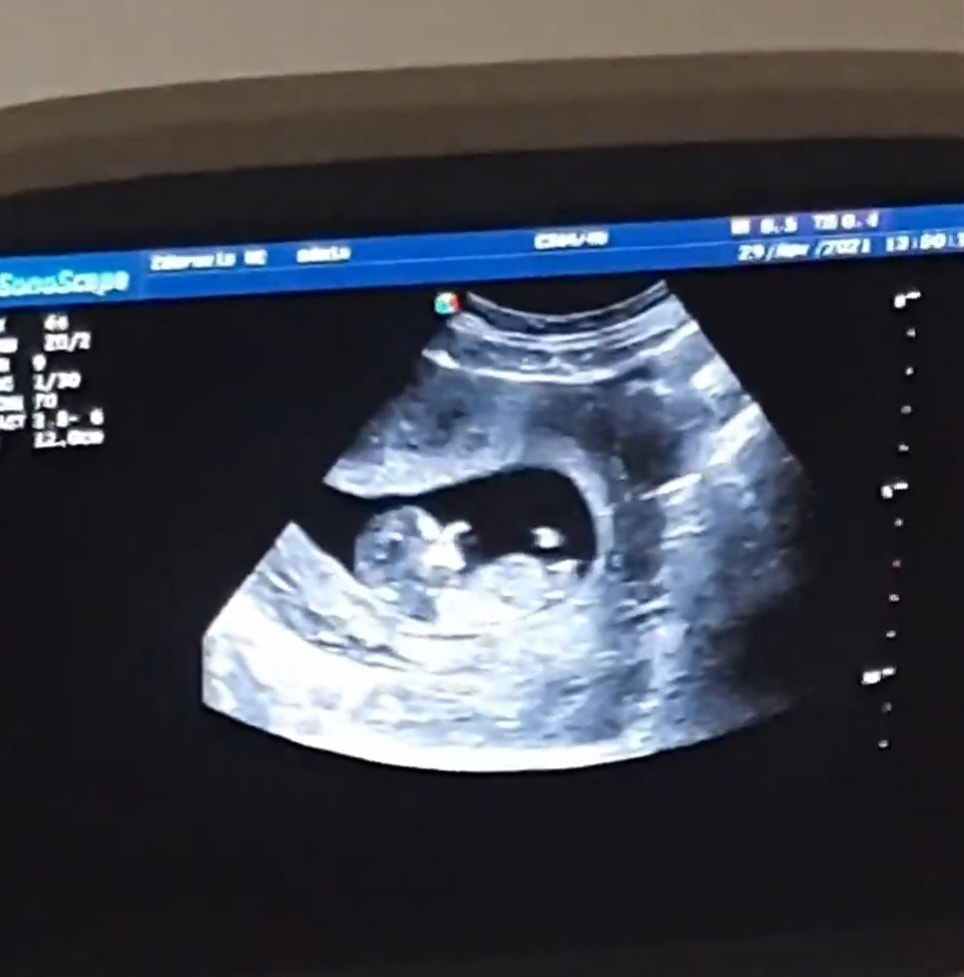

Манэ, а тут по бугорку кого видите?) Изображение

Анастасия, Ничего себе Прямой бугорок прям)🤭🤭 А срок на снимке какой?)

Манэ, 12 недель)

12 недель и 4 дня Определение пола на 13 недели